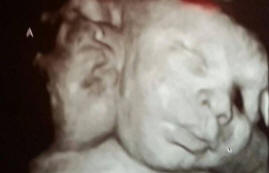

Takové děti – jeden z milionu, má dítě dvě samy fungující hlavy, ale jedno tělo a jedno srdce a rodiče velmi rádi doplníme rodinu.

Asa a Ali Hamley se narodili Robinovým třiceti čtyřům rodičům a Michelle. V jazyce medicíny se jejich odchylka nazývá dicefální parapagus, to je stav dvojčat, když jsou všechny orgány mimo kromě cílů mají společné.

Tento případ je zajímavý, protože obvykle takové děti nepřežijí. V jednom z tisíců případů může žena s takovým dítětem otěhotnět, ale jen jedno dvouhlavé dítě na milion běžných dětí dokáže přežít.

Asa a Eli mají tři plíce, s výjimkou těch lehkomyslných poruchy v srdci, jejich tělo je v perfektním pořádku.

Vzhledem k tomu, že téměř všechny orgány a oběhový systém dvojčata sama pro dva, nelze je rozdělit a zachránit tak život oběma.